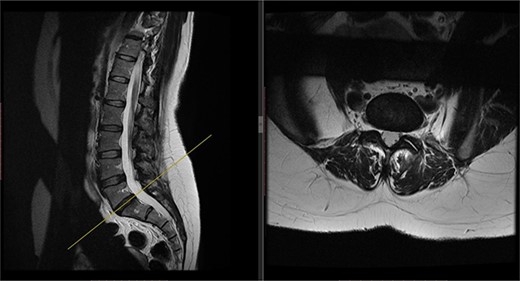

A repeat MRI scan (Fig. 2) performed in December 2016 did not show any interval changes as compared to the scan performed in February 2016. The patient presented elsewhere and was recommended for spinal fusion surgery. A posterior pedicle screw instrumentation with rods and a posterior interbody cage procedure was performed elsewhere in January 2017.

Preoperative MRI of the lumbar spine performed in December 2016. The MRI shows no neurological compression.